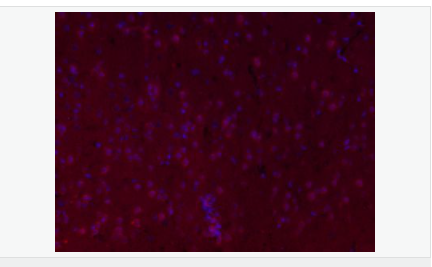

交叉反應:Mouse,Rat(predicted:Human,Pig) 推薦應用:IHC-P,IHC-F,IF,ELISA

| 產品應用 | ELISA=1:5000-10000 IHC-P=1:100-500 IHC-F=1:100-500 IF=1:100-500 (石蠟切片需做抗原修復) not yet tested in other applications. optimal dilutions/concentrations should be determined by the end user. |